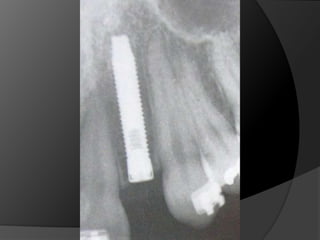

Diagnóstico y Planificación MultidisciplinariaHistoria ClínicaAnamnesisFotografía clínica Montaje modelos de estudioEncerados DiagnósticosEvaluación Radiográfica Radiografías PeriapicalesRadiografía PanorámicaEvaluación DentalEvaluación PeriodontalEvaluación EndodónticaEvaluación OclusalEvaluación Articular?

EVALUACIÓN DE PILARESProporción corona-raizConfiguración de la raízZona del Ligamento Periodontal (Ley de Ante)

Tylman: afirmó que dos dientes pilares son capaces de soportar dos póntIcos.Johnston y col.: LEY DE ANTELa superficie radicular de los dientes pilares, con soporte óseo periodontal, debe ser mayor o igual a la de los dientes a sustituir con pónticos

Diagnóstico y PlanificaciónMultidisciplinariaHistoria ClínicaAnamnesisFotografía clínica Montaje modelos de estudioEncerados DiagnósticosEvaluación Radiográfica Radiografías PeriapicalesRadiografía PanorámicaEvaluación DentalEvaluación PeriodontalEvaluación EndodónticaEvaluación OclusalEvaluación Articular?